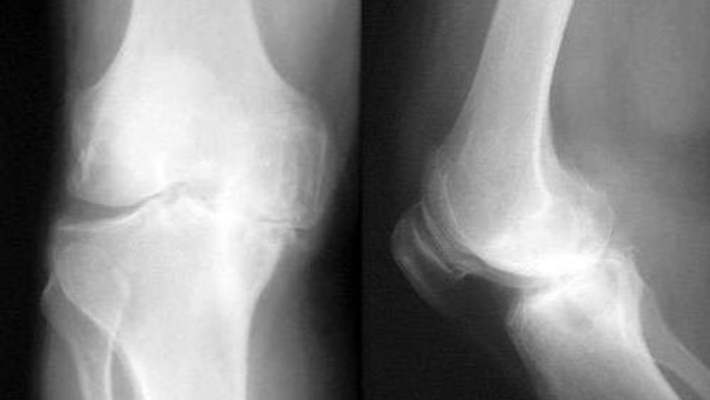

- Bir diz çıkığında neredeyse her zaman ağır bağ dokusu yırtılmaları vardır ve bazen diz kemiğinde de kırıklar oluşur. Sıklıkla bacaktaki dolaşımı onarmak için, acil tamir gerektiren kan damarı yaralanmaları da görülür. Şişme kaybolduktan sonra, diz ekleminin tekrar fonksiyon gösterebilmesi için ameliyata ihtiyaç olabilir. Bir kemik uzmanının (ortopedist) yaralanmadan sonra sizi görmesi gerekir.